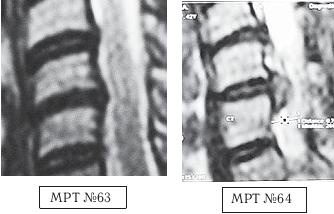

На МРТ № 63 наблюдается фрагмент шейного отдела позвоночника. На данном уровне отчётливо видно исправление лордоза, стеноз спинномозгового канала, небольшие протрузии практически компенсированные спондилёзом в сегментах СV-СVI, СVI—СVII, гипертрофия задней продольной связки на данном уровне.

На МРТ № 64 наблюдается фрагмент шейного отдела позвоночника той же пациентки через два месяца.

На снимке видно, что к имевшимся (на МРТ № 63) проблемам добавилась ещё и грыжа в сегменте СV-СVI, и секвестрированная грыжа межпозвонкового диска в сегменте СVI-СVII..

Вот ещё один пример. Произошло это несчастье по причине того, что в течение двух месяцев данной пациентке в одном из специализированных центров врач «вертебролог-вертеброневролог» проводил вытяжения шейного отдела позвоночника с применением петли Глиссона на наклонной плоскости под силой тяжести собственного веса самой пациентки. На жалобы пациентки о том, что после нескольких сеансов самочувствие ухудшилось и усилились боли, врач объяснял, что «это нормально, просто позвонки растягиваются, и межпозвонковые диски становятся на место, поэтому происходит обострение». Но после того как данная пациентка во время очередного сеанса потеряла сознание, ей сделали контрольное МРТ шейного отдела позвоночника (МРТ № 64, была обнаружена секвестрированная грыжа межпозвонкового диска), а затем в срочном порядке направили в нейрохирургию. Этот случай свидетельствует о некомпетентности этого врача «вертебролога-вертеброневролога» и ещё раз подчёркивает, насколько важно в нашем обществе самому пациенту владеть информацией о своём позвоночнике, о процессах, в нём происходящих, и о способах лечения.